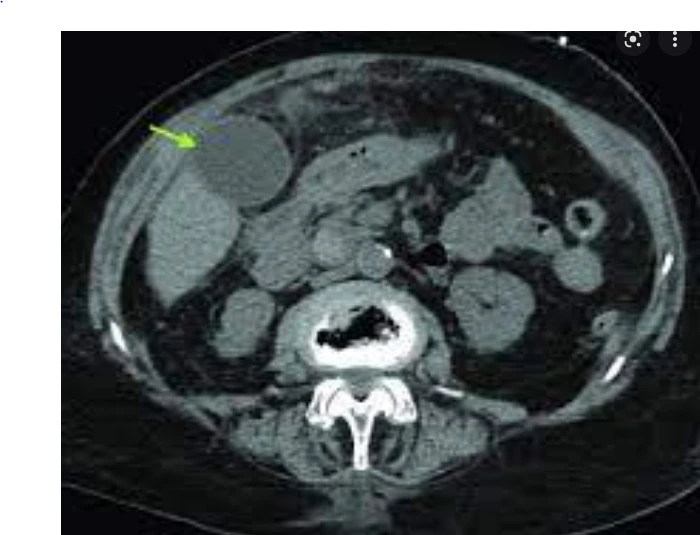

복부 CT, MRI의 경우 금식을 통해 담낭을 부풀려 검사를 해야 한다. 음식을 먹을 경우 담낭에서 담즙을 짜주게 되어, 담낭이 협착된다. 담낭 내부가 보이지 않으면 담낭에 있는 용종이나 돌, 염증 상태 등을 평가할 수 없다. 더불어 금식이 되지 않은 경우 장운동으로 인해 한 단면을 찍는 영상 검사가 부정확해질 수 있다.

초록색 화살표의 동그란 원이 담낭이다. 금식이 되지 않을 시엔 보이지 않는다.